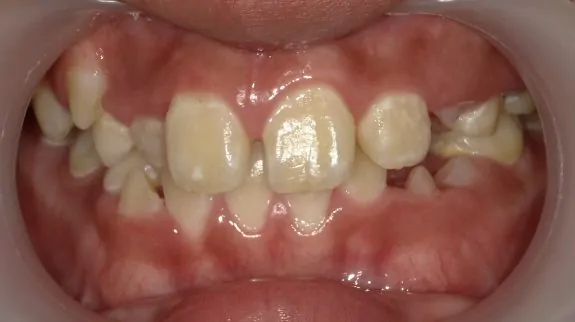

治療前

診断名・主な症状

八重歯・前歯のガタガタ

年齢

11歳女児

口腔衛生指導後、マウスピース型矯正歯科装置にて歯の移動を行いました。右上の犬歯の生えるスペースがありませんでしたから、歯を移動することで排列スペースをつくっています。Ⅰ期治療が終了したところで、ご本人と保護者の方が満足されているため経過観察中です。すべての永久歯が萌出したところで、セカンドフェーズ(Ⅱ期治療)を行うか判断する予定です。